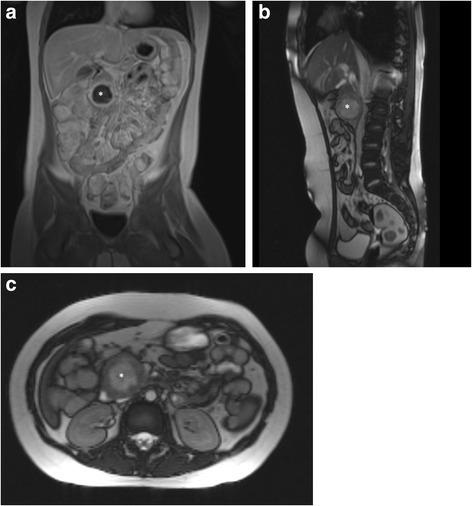

Herein we report the case of an 8 - year old child presenting with symptoms of gastric outlet obstruction.

A solid pseudopapillary neoplasm of the pancreatic caput was diagnosed and surgically removed.

在此我们报告一例8岁儿童出现胃出口梗阻症状的病例。

诊断为胰头实性假乳头状肿瘤并进行了手术切除。